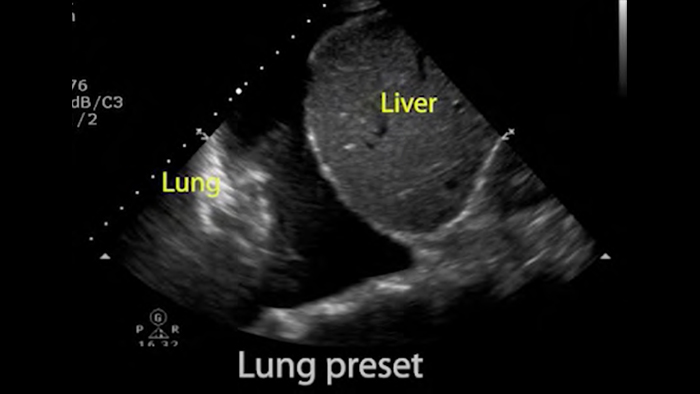

As soluções do Lumify para POC podem ajudar você a detectar o tubo endotraqueal na traqueia, auxiliar em procedimentos de cricotireotomia, diagnosticar derrame pleural e doenças alveolares intersticiais.

• Faixa de frequência operacional de 1 a 4 MHz • 2D, Doppler colorido, modo M, XRES avançado e imagem harmônica • Diagnóstico por imagem de alta resolução para aplicações abdominais e cardíacas: otimizações predefinidas de diagnóstico por imagem cardíaco, obstetrico/ginecológico, pulmonar, abdominal e FAST • Novidade para Android: Doppler Pulsado